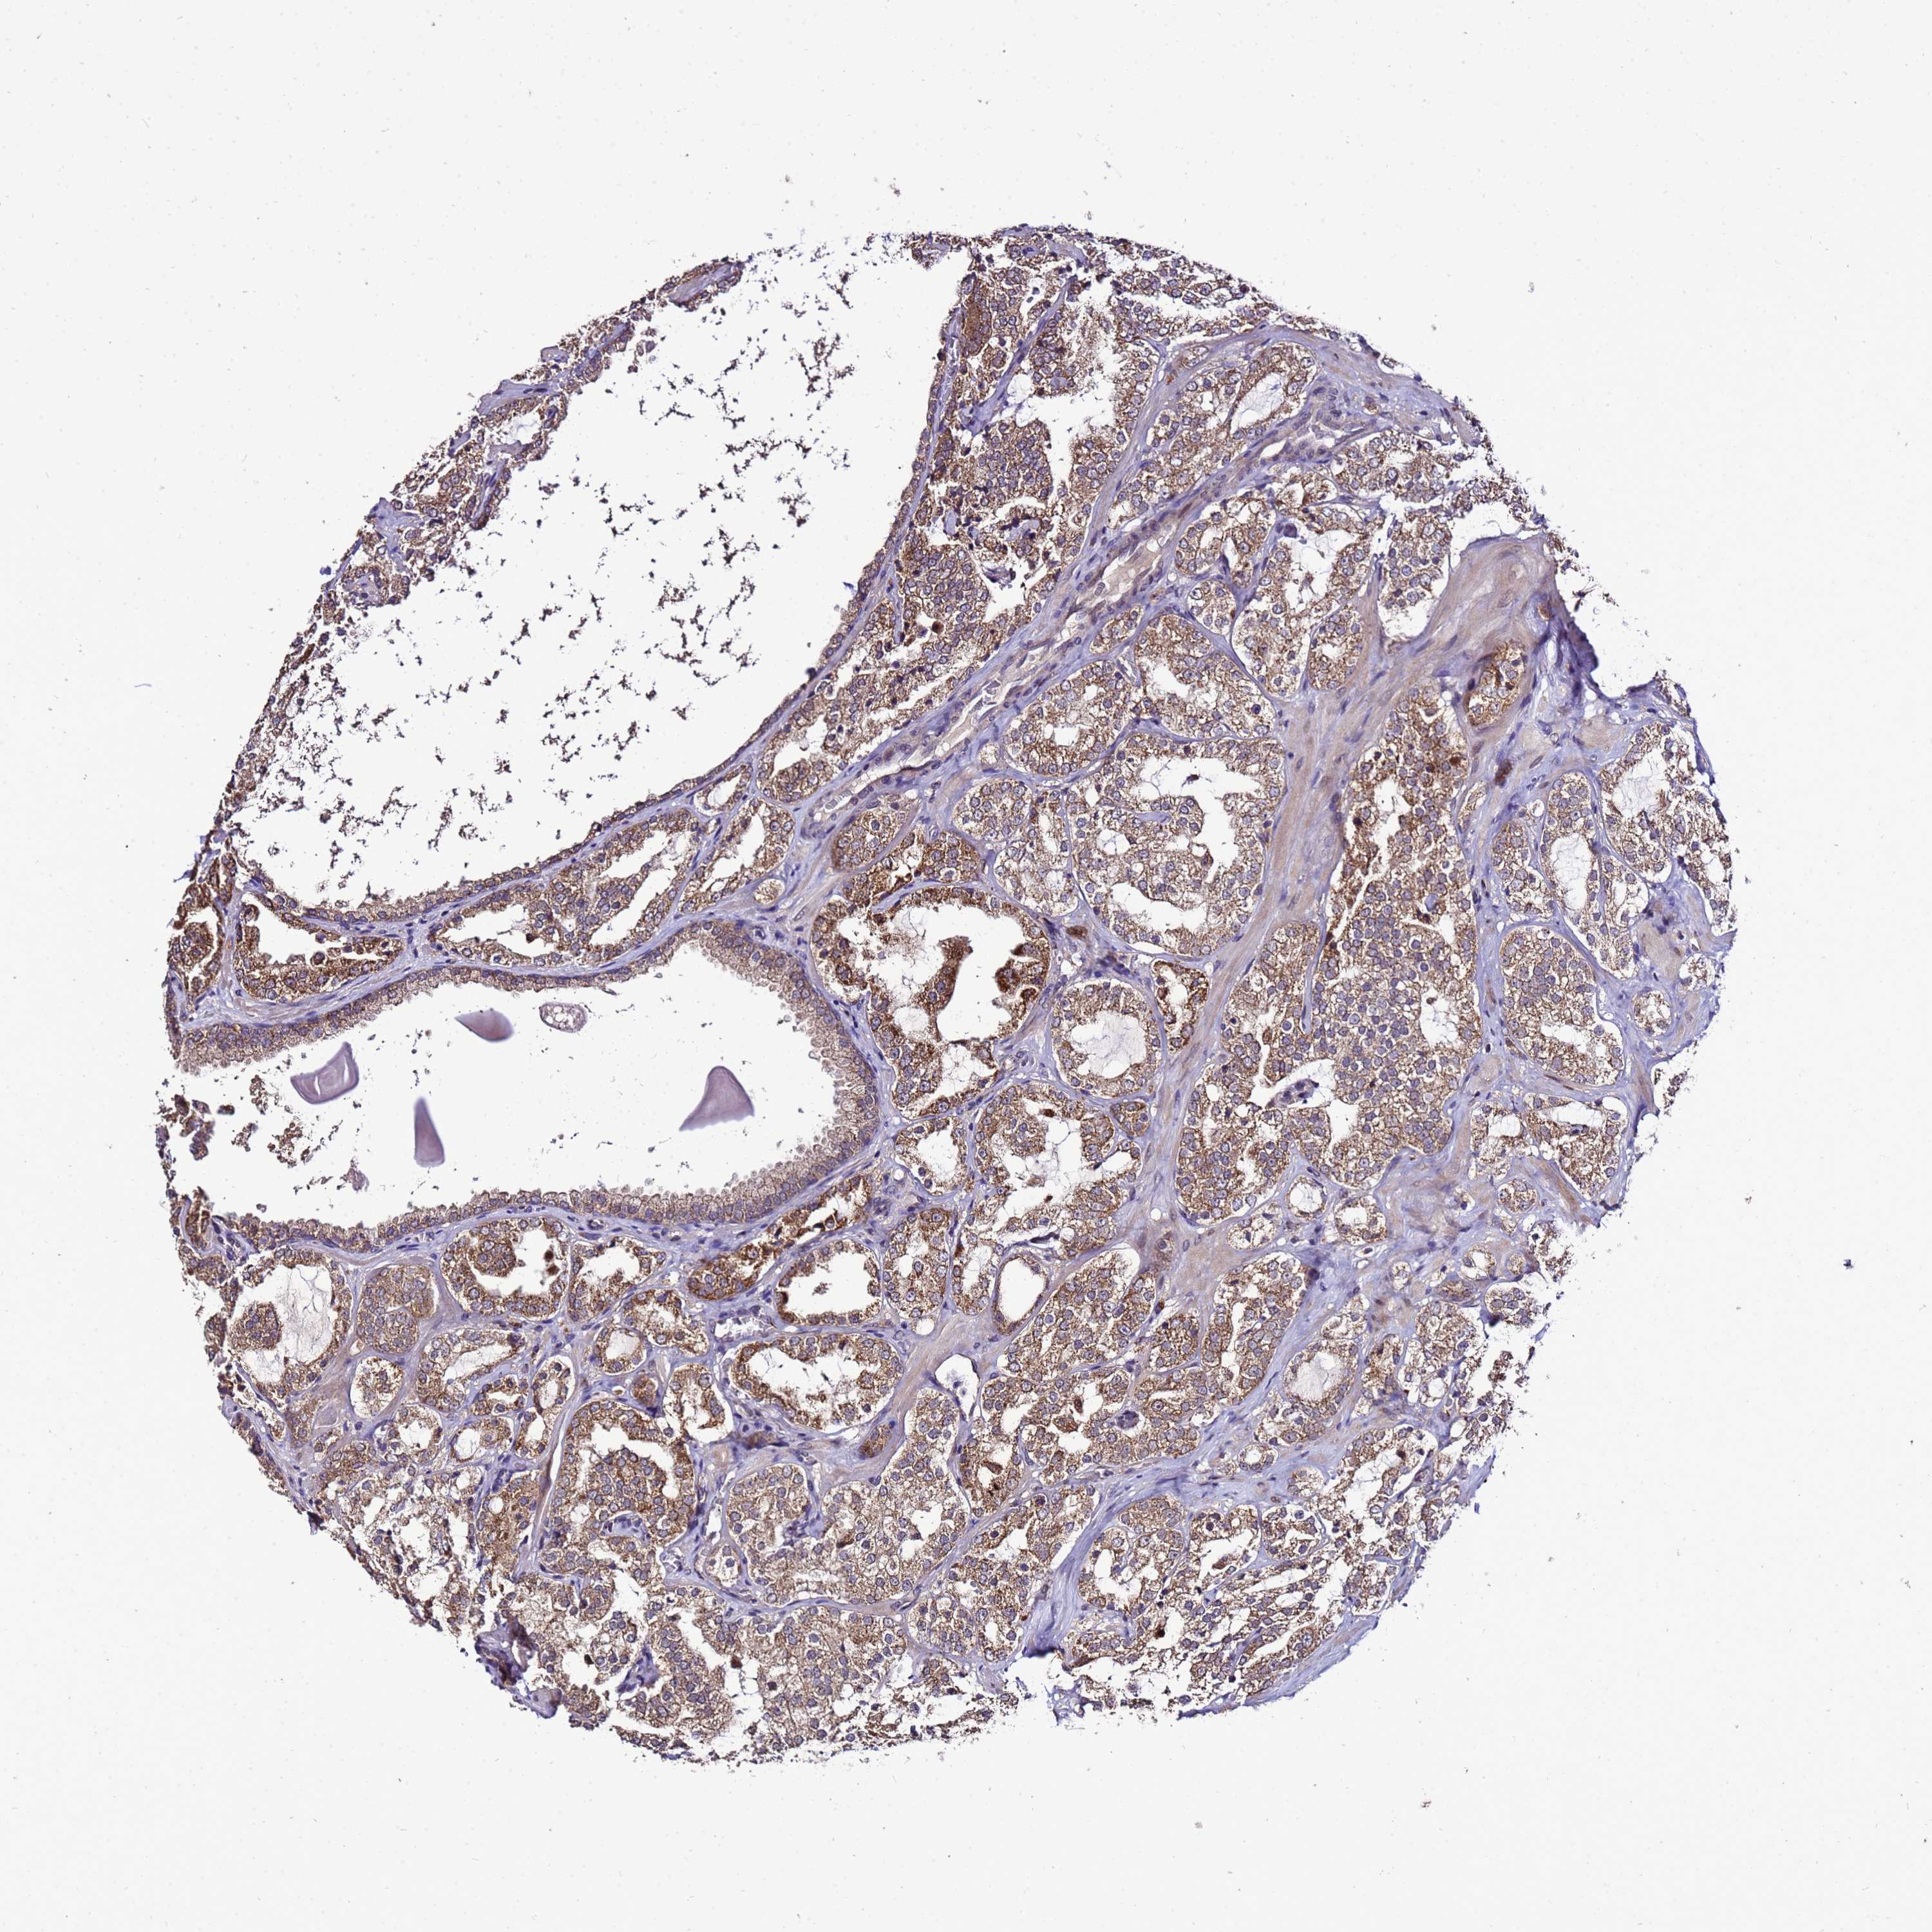

PROSTATE CANCER - Protein expressioni

A mouse-over function shows sample information and annotation data. Click on an image to view it in a full screen mode. Samples can be filtered based on level of antibody staining by selecting one or several of the following categories: high, medium, low and not detected. The assay and annotation is described here.

Note that samples used for immunohistochemistry by the Human Protein Atlas do not correspond to samples in the TCGA dataset.

Antibody stainingi

Antibody staining in the annotated cell types in the current human tissue is reported as not detected, low, medium, or high, based on conventional immunohistochemistry profiling in selected tissues. This score is based on the combination of the staining intensity and fraction of stained cells.

Each image is clickable and will lead to virtual microscopy that enables deeper exploration of all samples and also displays staining intensity scores, fraction scores and subcellular localization as well as patient and tissue information for each sample.

Antibody HPA044373

Staining

High

Medium

Low

Not detected

Intensity

Strong

Moderate

Weak

Negative

Quantity

>75%

75%-25%

<25%

None

Location

Nuclear

Cytoplasmic/membranous

Cytoplasmic/membranous,nuclear

Adenocarcinoma, NOS

Adenocarcinoma, High grade

Adenocarcinoma, Low grade